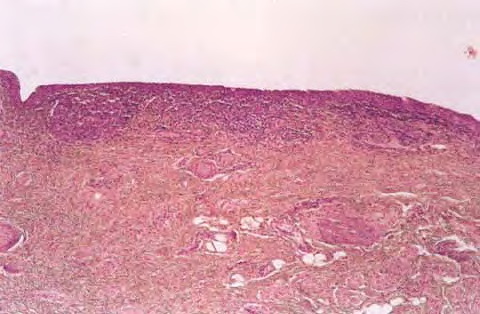

Scondary syphilis = الافرنجي الثانوي